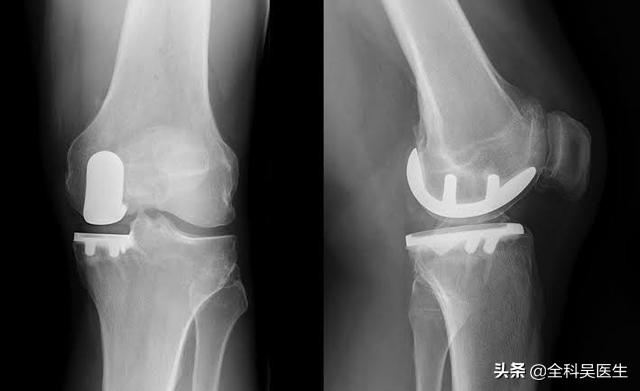

● Si les symptômes de l'articulation sont particulièrement sévères et que le patient a développé une...Déformations articulaires évidentesSi vous êtes incapable de marcher normalement, si vous ressentez des douleurs articulaires importantes lorsque vous marchez plus de 500 mètres et si vous êtes gravement affecté par des douleurs au repos ou pendant votre sommeil, il y a une indication pour une prothèse articulaire.L'arthroplastie du genou peut être le seul moyen d'aider complètement le patient.。

9. remplacement du genou :Si l'arthrose a entraîné une déformation évidente de l'articulation, qui affecte gravement le traitement de la vie du patient, le moment est venu de résoudre complètement le problème du patient par la mise en place d'une prothèse de genou.

Apparition tardive : articulations artificielles pour soulager la douleur sévère

Aux stades avancés de la maladie, le cartilage du patient est presque usé. Sans l'amortissement du cartilage, les os frottent directement l'un contre l'autre. À ce stade, les seules options sont de remplacer l'articulation par une prothèse ou de procéder à une arthrodèse, qui est rarement utilisée car elle peut affecter gravement la mobilité du patient après l'opération.